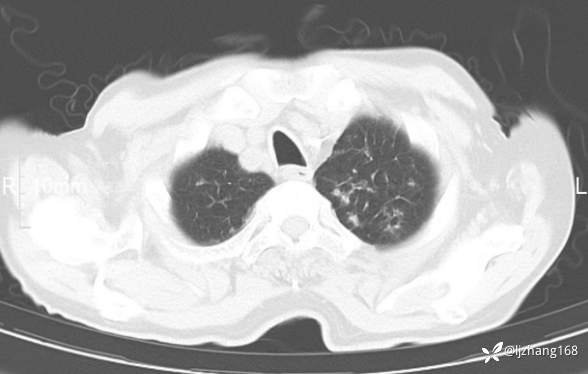

辅助检查:胸部CT:双肺肺气肿,间质性病变,血气分析:PH 7.413, PCO2 29.2mmHg, PO2,81.8mmHg,乳酸 3.3mmol/1,剩余碱-4.0mmol/1,HC03 18.8mmol/1。全血超敏C反应蛋白:超敏C反应蛋白 135.60 mg/L、 白细胞 14x19^9/L,中性粒细胞11.6x10^9/L。